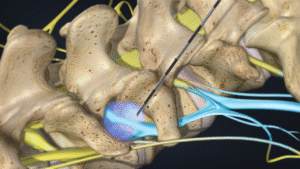

- Minimal-invasive Eingriffe

- Neuromodulation